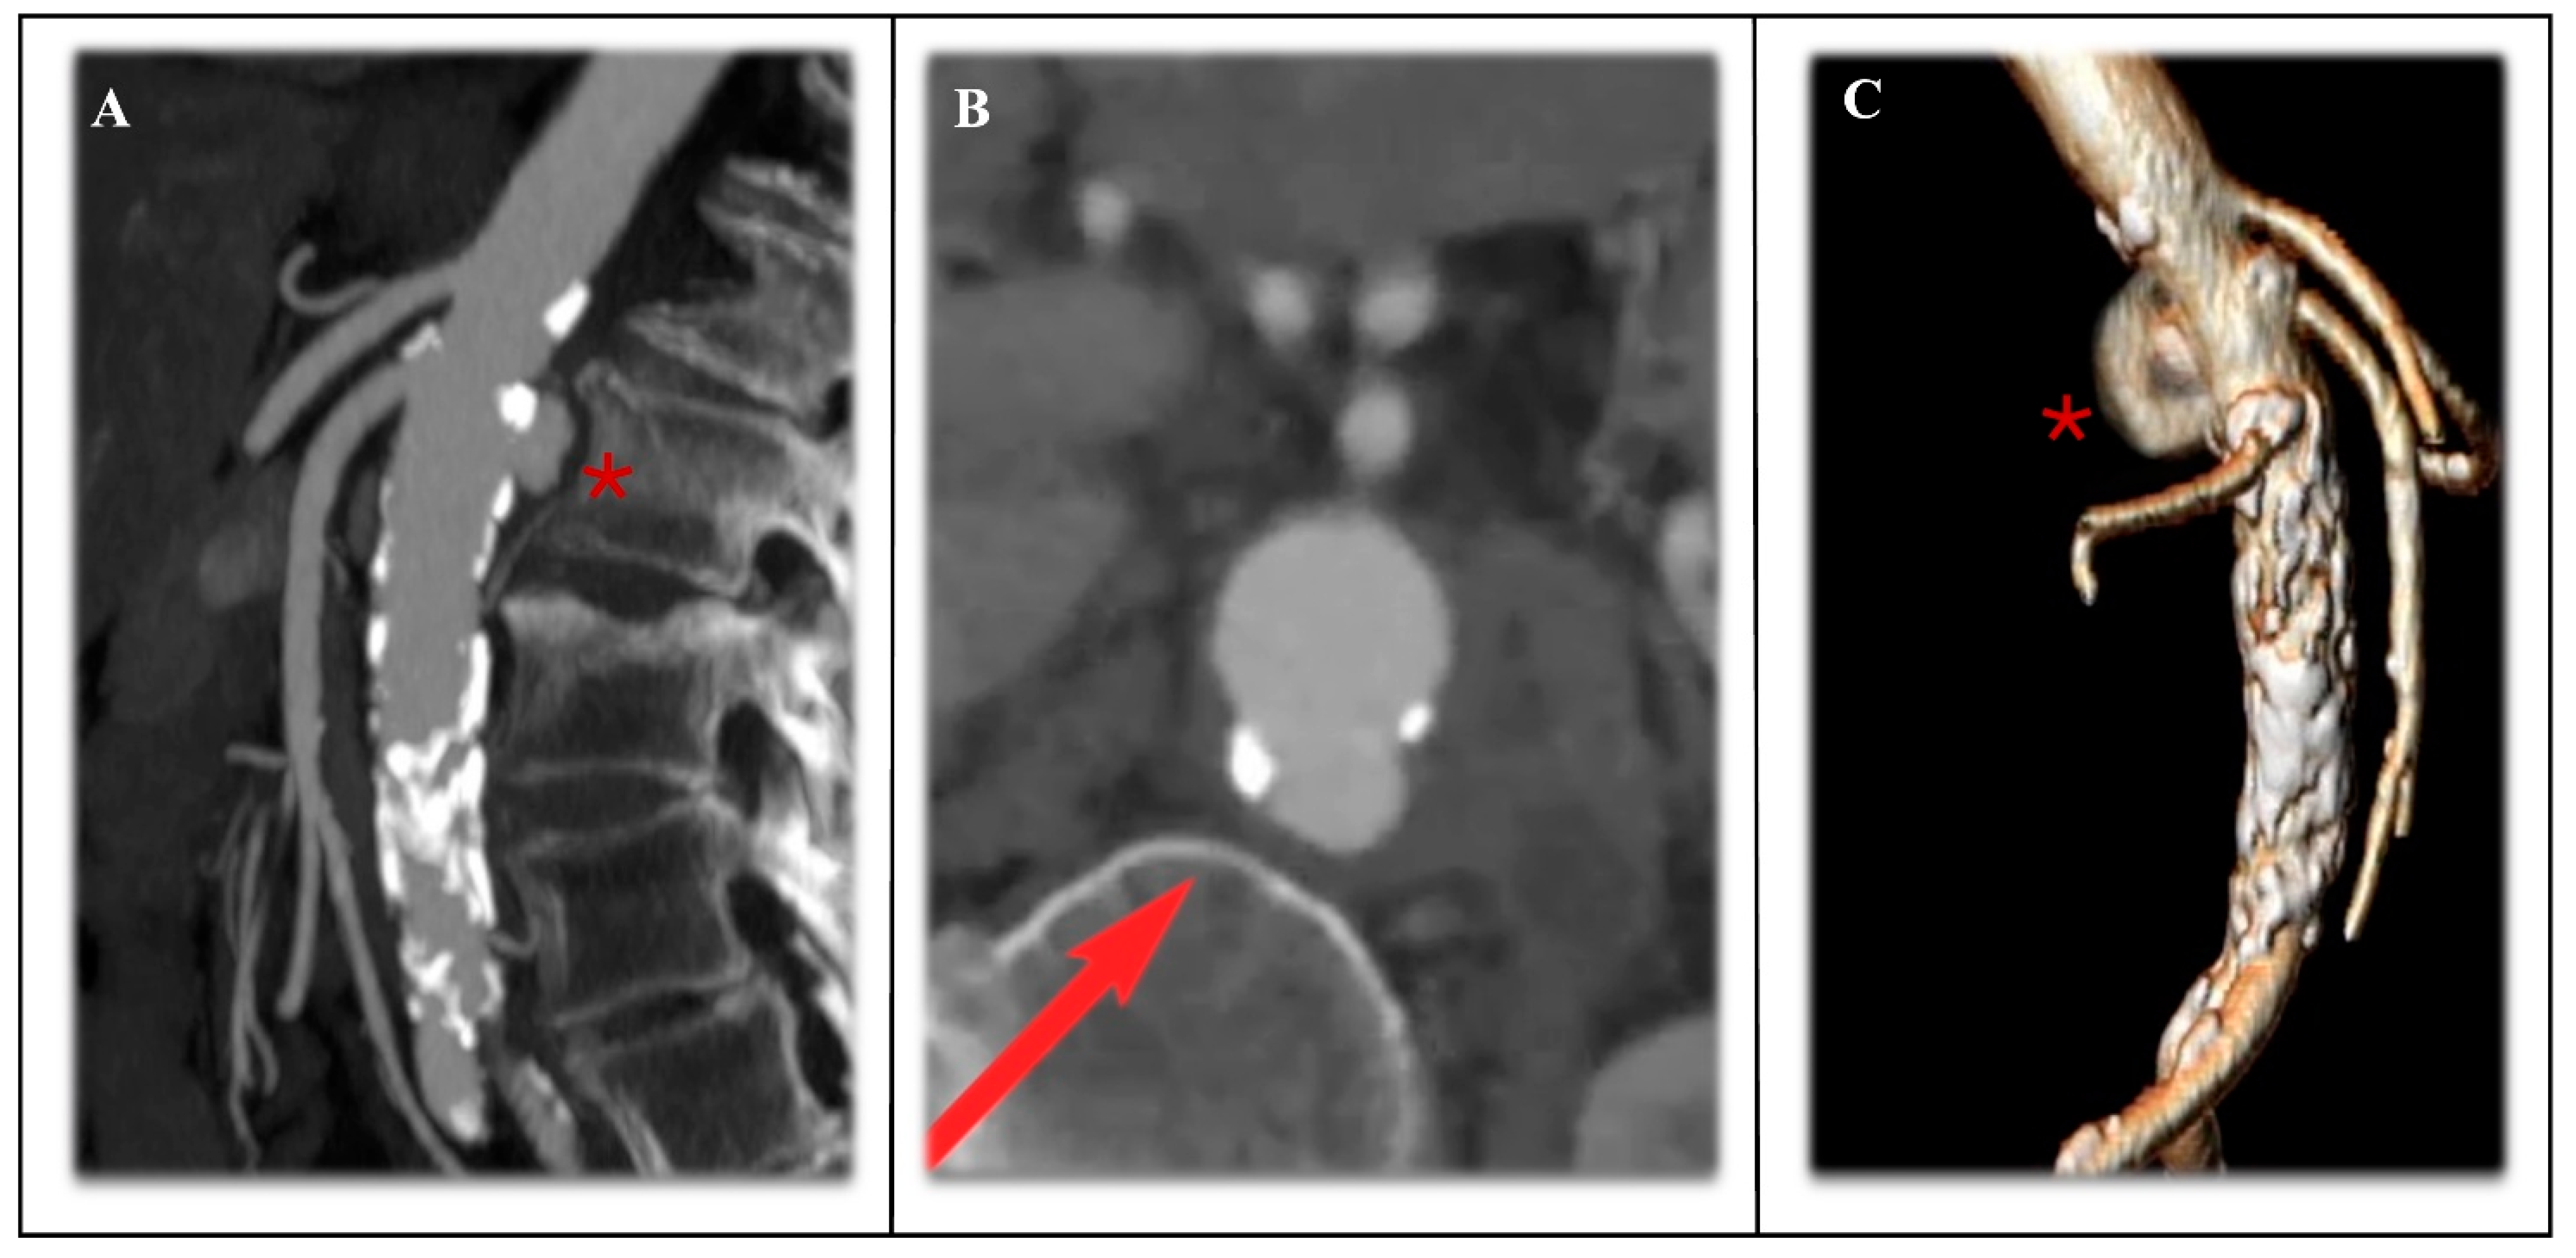

4.2. Fenestrated-Branched Options for Disease Involving the Para-Visceral Aorta